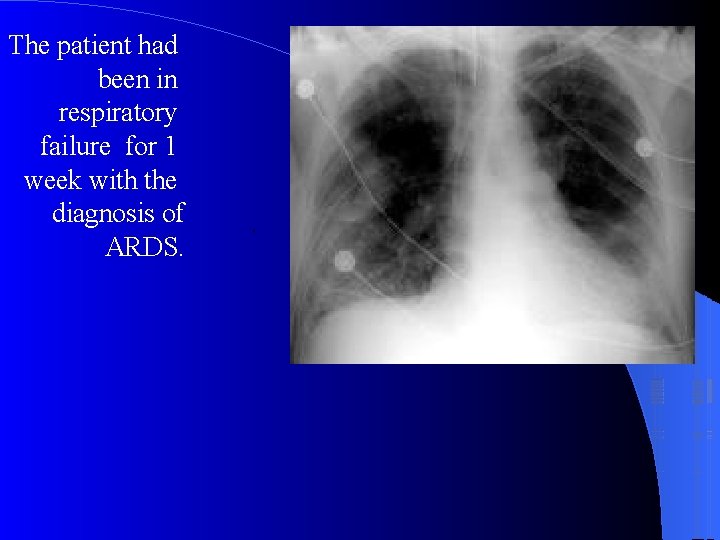

CXR Chest radiographic findings are non-specific and resemble those of typical pulmonary edema or pulmonary hemorrhage. There are diffuse bilateral coalescent opacities (the only radiological criterion defined by the Consensus Conference). The time course of ARDS may help in differentiating it from typical pulmonary edema. Chest x-ray features usually develop 12 -24 hours after initial lung insult as a result of proteinaceous interstitial edema. Within one week, alveolar pulmonary edema (hyaline membrane) occurs due to type 1 pneumocyte damage. In contrast to cardiogenic pulmonary edema, which clears in response to diuretic therapy, ARDS persists for days to weeks.

The patient had been in respiratory failure for 1 week with the diagnosis of ARDS. .

chest radiographic findings in a patient with ARDS that evolved over approximately 1 week